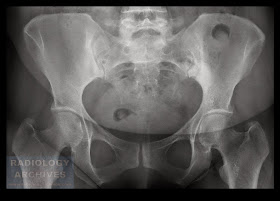

Πυκνωτική Οστεΐτιδα Λαγονίου

Osteitis Condensans Ilii